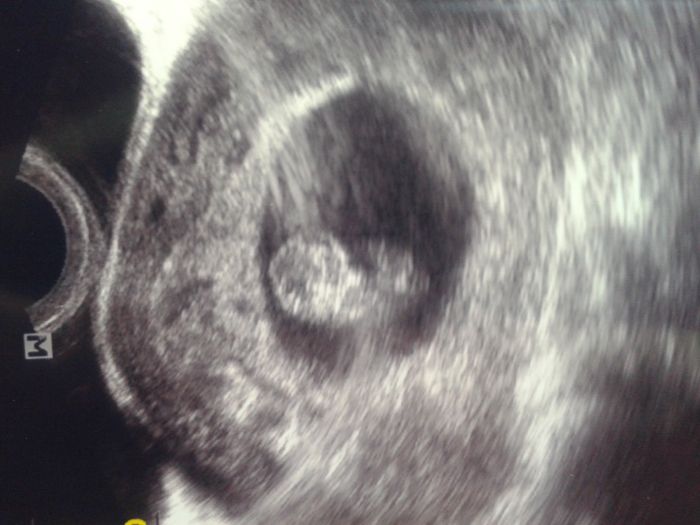

. Dopadli jsme dobře, dle MS 9+1 a dle ultrazvuku 8+6, čili se budeme řídit dle ultrazvuku (tak rozhodl pan doktor). Srdíčko bije o závod a vše je ok. Spadl mi kámen ze srdce a v červnu se chystám na screening v 1. trimestru. Přidám foto, ve skutečnosti jde lépe vše vidět, jen foťák v telefonu mi to nechce pěkněji vyfotit.. Kontrola za 4 týdny..

Jo a máme 22 mm

[743688] no super, krásná fazolka!